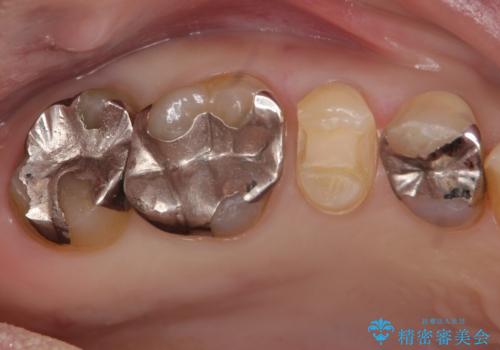

- 詰め物が欠けたとのことで来院されました。

実際は詰め物ではなく歯自体が欠けている状態でした。

銀の詰め物を外し、欠けたところを覆うように新しい詰め物を作成します。

欠けたところに金属を使用することで、再度欠けてしまうリスクを抑えました。